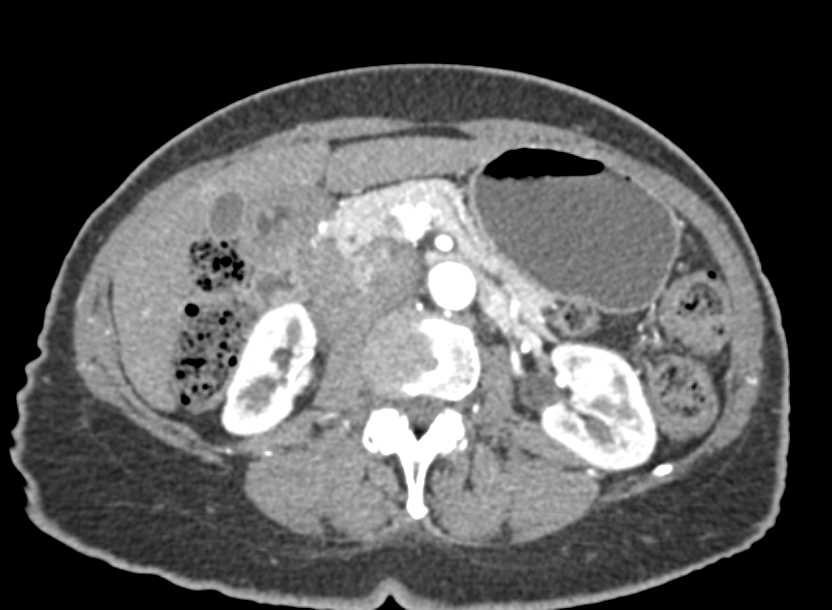

Pneumatosis of the Right Colon